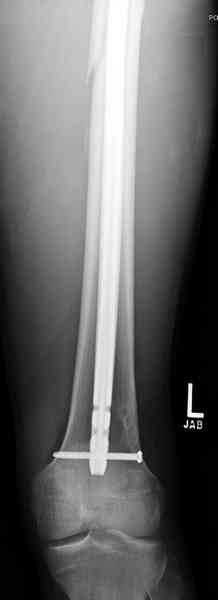

В нашем случае 21 летний боец уличного фронта, фиксацию провели на следующий день, зафиксирован интрамедуллярным штифтом. Не стали делать первичную хирургическую обработку точечной раны, зафиксирован как есть. Клинические снимки:

Имя     : 1.jpg

Тип     : image/jpeg

Размер  : 15252 байтов

Описание: отсутствует

Url     : http://weborto.net:8080/pipermail/ortho/attachments/20081023/35009bb3/attachment-0009.jpg